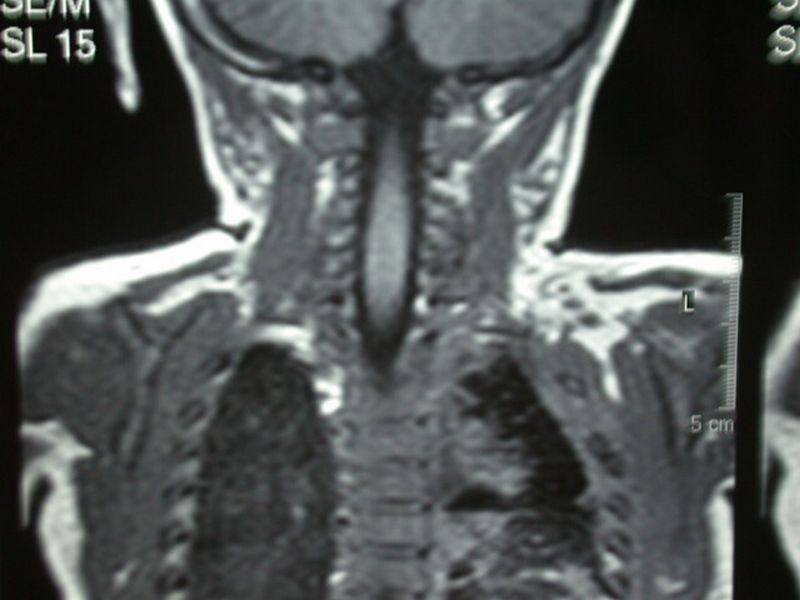

5. Brachial Plexus surgery